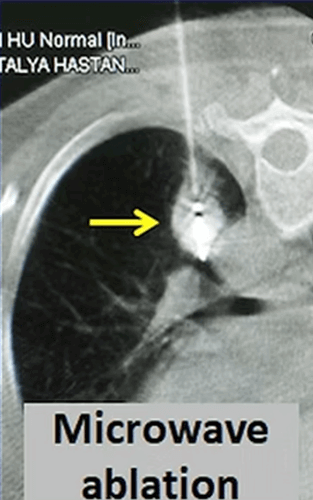

In our patient with a 3 cm tumor (*) in his left lung, microwave ablation was performed using two antennas. The PET-CT taken at 4 months after the procedure shows that the tumor has shrunk markedly and its activity disappeared almost completely.

Another ablation method that has become popular in lung cancer in recent years is microwave. Microwave ablation provides a faster and stronger ablation than radiofrequency. However, unlike liver, there is not enough information about the efficiency and complication rates in the lung. In microwave ablation, the microwave antenna is placed in the center of the tumor with CT guidance and the tumor is ablated for 3-10 minutes under general anesthesia or deep sedation. For microwave, tumors that are located in the middle of the lung and less than 3cm in diameter are more suitable.

In our female patient who had metastases of salivary gland cancer in her lung, microwave ablation was performed to the largest mass with a diameter of 2 cm. One year later, the follow-up CT reveals only a small fibrotic remnant (arrow).